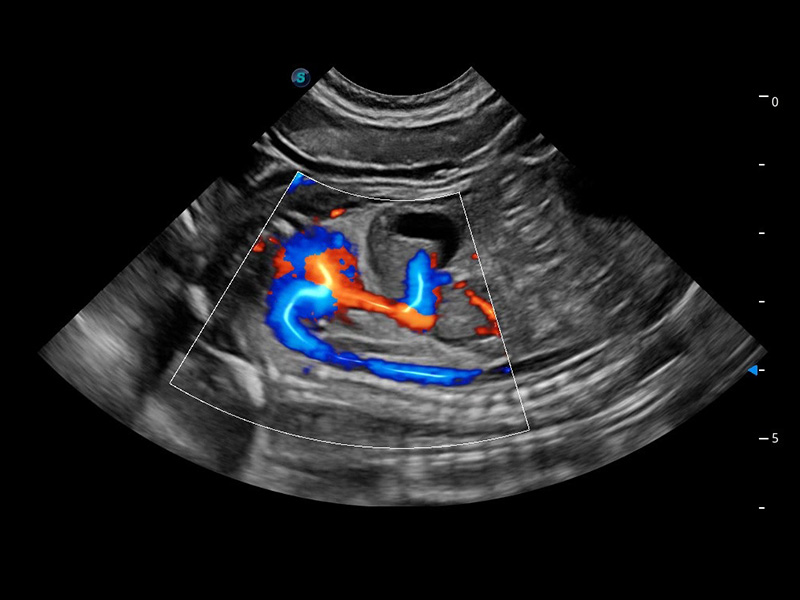

ProPet 60 作为一款高端台式动物超声设备,为动物医生的日常诊断提供了一系列贴合动物临床需求、解决临床实际问题的高级成像功能。凭借全系列高清探头,满足医生对腹部、心脏、生殖、浅表、肌骨等成像的所有需求,切实帮助您提升检查效率,提高诊断信心。

动物是人类最亲密的朋友和最值得信赖的伙伴。亚星官网也一直致力于探索动物专用的超声影像解决方案。 全新推出的ProPet系列,是亚星官网在动物超声影像智能化、专业化、精准化的一次跨越式革新。动物不能用言语来表述自己的不适,通过超声影像,ProPet系列搭建了动物医生与不同物种沟通的“桥梁”,为动物医生注入了“治愈之力”。